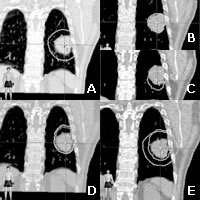

图A为吸气末常规CT所示计划靶区(PTV)。图B、图C和图D分别为吸气末、呼气末和整个呼吸期间的4D-CT图像。图E为常规CT与4D-CT的PTV对比。可见,常规CT漏掉了呼气末肿瘤涉及的部分区域。